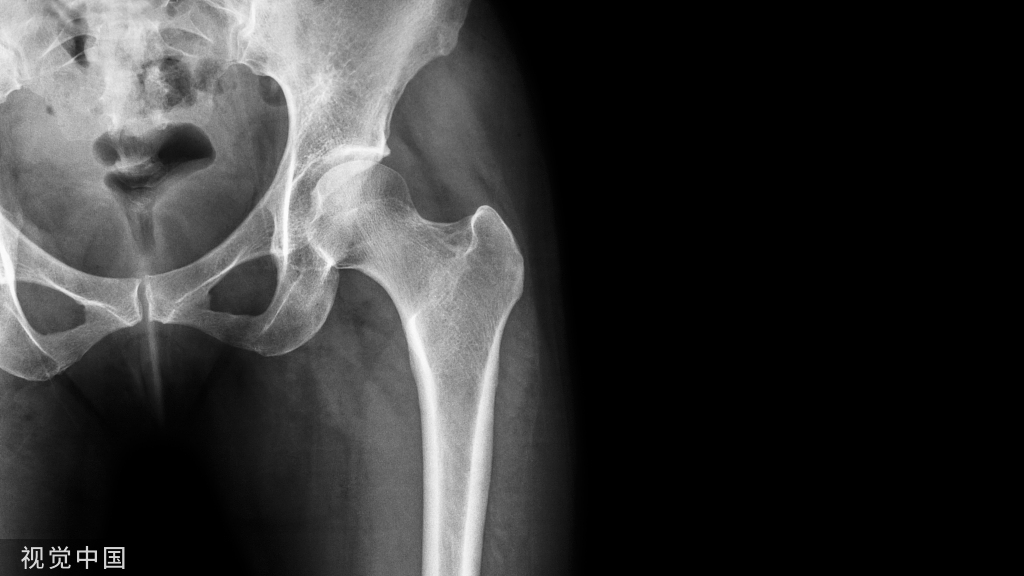

因为皮质穿透多,一定要把钉道做的足够长,否则钉子拧入过程中阻力太大且易跑偏。可以全程将长导针插入钉道攻丝、拧钉。螺钉长度至少70mm~80mm 。